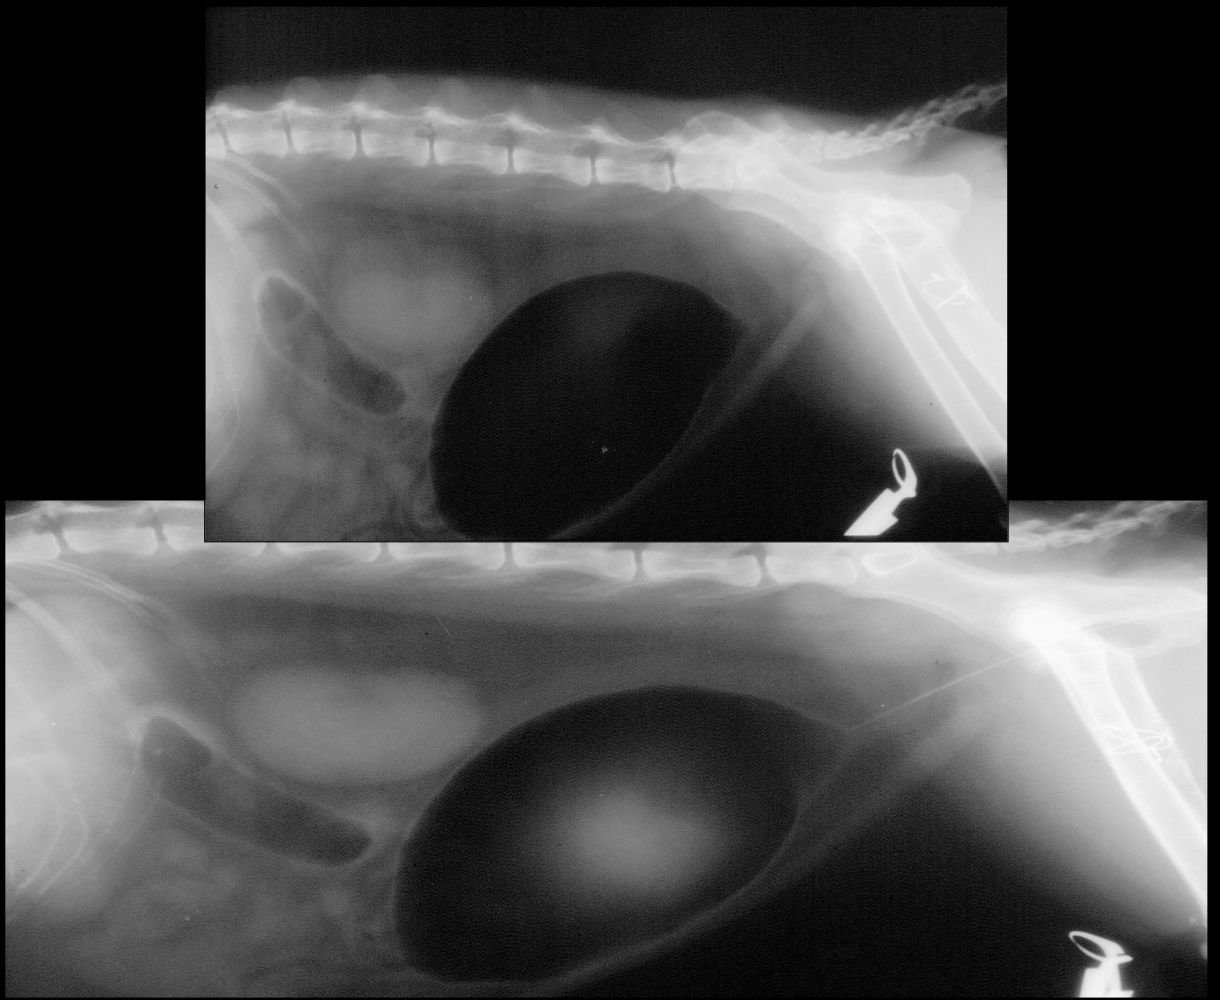

What is being pointed to in this cystourethrograph?

negative gas contrast with positive iodine contrast in the middle

What is seen in this cystourethrograph?

negative gas contrast only